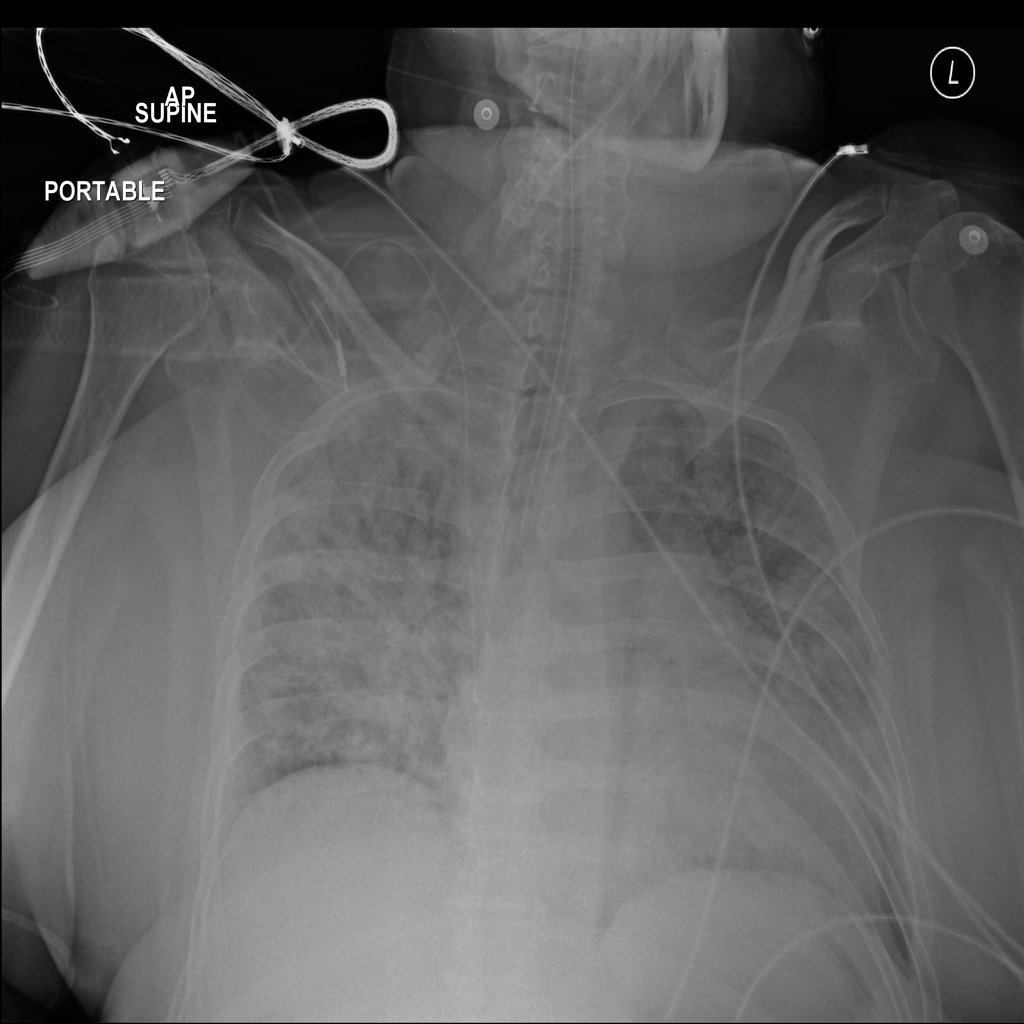

PAT-B3C3 · IMG-001Pneumonia

PAT-B3C3 · IMG-001

PA